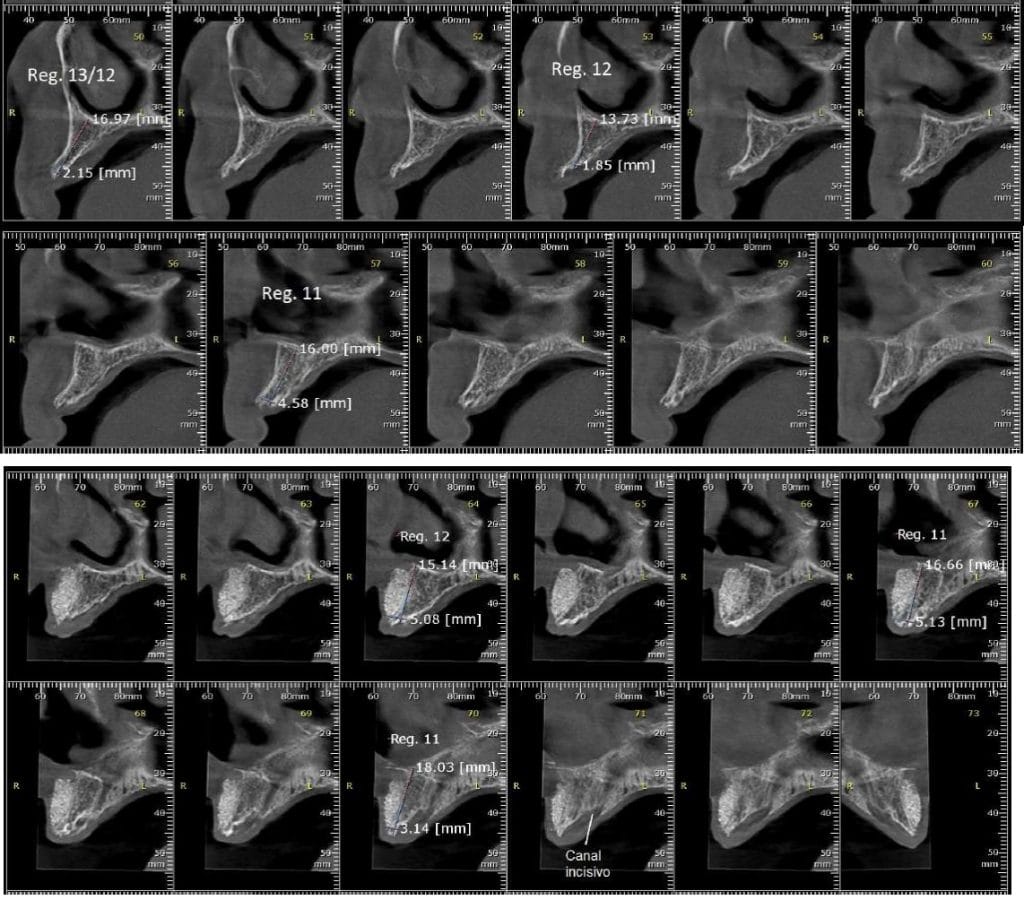

Olá colegas, aqui está um caso didático de reconstrução óssea total da maxila, levantamento do seio maxilar bilateral e bloqueio espesso com aplicação do conceito de PRF e Biotensigrity.

SEM tela, SEM parafusos, SEM membranas de colágeno. Substitua apenas osso aloplástico e sangue.

Após 6 meses de maturação óssea e implantes instalados com torque médio de 35 N / cm2.